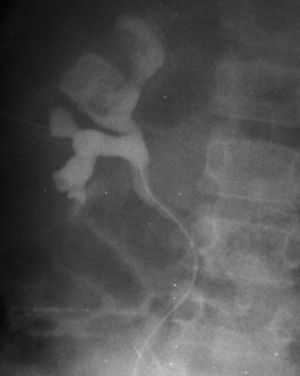

De los pacientes diagnosticados de carcinoma de células renales (n= 4) (con edad y presentación mostrados en la tabla 2) en dos casos se localizaron masas renales en la corteza renal, con infiltración del sistema pielocalicial. De estos dos, uno demostró fuga de contraste del sistema excretor en la radiografía abdominal post-TC con contraste, y el otro invasión de médula con extensión hasta el uréter proximal (fig. 5). En un único caso se apreciaron abundantes calcificaciones grumosas intratumorales dispersas (fig. 6).

Fig. 6. Carcinoma de células renales. Urografía intravenosa que muestra una masa en hemiabdomen izquierdo, con abundantes calcificaciones grumosas dispersas, que desplaza el sistema pieloureteral.